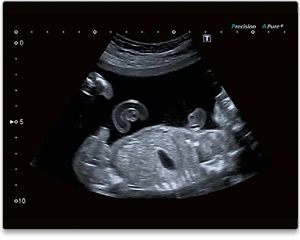

- 3D-Ultraschall-Untersuchungen, wodurch das frühzeitige Erkennen des kindlichen Geschlechts wesentlich erleichtert wird.

- Herstellung von schönen 3D-Fotos des Babys im Mutterleib.